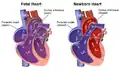

As the umbilical vessels are obliterated and the infant starts breathing at birth, the source of oxygen changes from the placenta to the lungs. This major trigger will facilitate the transformation from fetal to postnatal circulation in many ways.

First, the ductus venosus was previously kept open by the blood flow from the umbilical vein. The reduced blood flow through the umbilical vein at birth will collapse and close the ductus venosus. Hence, the IVC will only carry deoxygenated blood from the infant's organs and lower extremities. Second, as the infant breathes, the lungs will expand and fill the alveoli with oxygen. The increased oxygen content will dilate the pulmonary capillaries and also trigger the release of nitric oxide, which further dilates the blood vessels within the lungs. Together, these forces will decrease the pulmonary vascular resistance.[7]

With decreased resistance in the lungs, there will be increased blood flow to the lungs from the right ventricle of the heart through the pulmonary arteries, establishing the newborn's pulmonary circulation. With each of the newborn's breaths, blood perfuses the pulmonary capillary beds and undergoes oxygenation before exiting the lungs via the pulmonary veins and returning to the heart. Thus, as more blood flows through the pulmonary circulation, there will be a higher volume of blood returning to the left atrium from the lungs. The increased venous return will elevate the pressure of the left atrium until it exceeds the pressure of the right atrium. The difference in pressure between these two chambers of the heart will close the foramen ovale.

Lastly, due to the decreased pulmonary vascular resistance, the pressure of the pulmonary artery will fall until it is lower than the pressure of the aorta. Since blood flows from high to low pressure systems, the direction of blood flow across the ductus arteriosus reverses. As the oxygen-rich blood from the aorta flows across the ductus arteriosus to the pulmonary artery, the ductus arteriosus will constrict in response to the high oxygen content of the blood. While oxygen serves as a vasoconstrictor of the ductus arteriosus, prostaglandins can keep the ductus arteriosus open to maintain blood flow to the lower extremities in cases of hypoplastic left heart syndrome where the mitral valve is shut. The removal of the placenta, a source of prostaglandin, is another mechanism by which the ductus arteriosus closes at birth.[8] Within the next 2 to 3 weeks, the constriction results in decreased blood flow to the structure which induces the death of the tissue to keep the structure permanently closed.[9]

As a result of these changes, postnatal circulation will direct deoxygenated blood from the inferior and superior vena cava to the right heart, from which the blood will flow to the lungs via the pulmonary circulation. Blood will be oxygenated in the lungs and return to the left heart, which will pump oxygen-rich blood out through the aorta to supply the rest of the body via the systemic circulation.